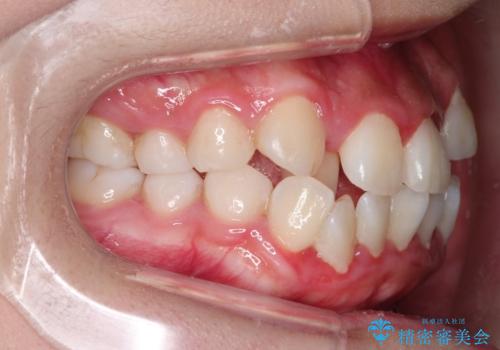

八重歯を改善!美しい口元を実現するハーフリンガル矯正

- 前歯のガタツキと口元のコンプレックスを解消するために来院されました。

ハーフリンガル矯正は、見た目を気にせずに矯正治療ができる方法です。この治療法は、八重歯や前歯のガタツキを効果的に改善します。特徴として、ワイヤーが上の歯の裏側に装着されるため、装置が外から見えません。これにより、治療中も自然な笑顔を保ちながら安心して治療を続けることができます。歯並びの悩みを持つ方にとって、非常に魅力的な選択肢です。